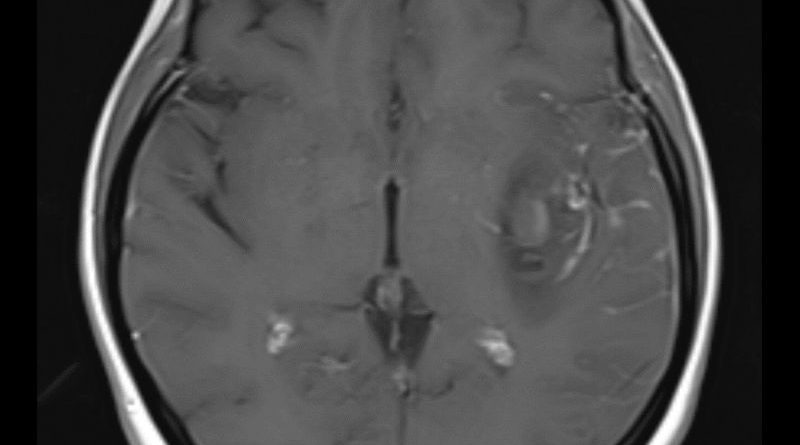

40 yaş, K

Ateş, bir haftadır artan baş ağrısı, yeni gelişen bilinç bulanıklığı

Sol MCA Segmet M2-3’te Sakküler Mikotik Anevrizma Rüptürü